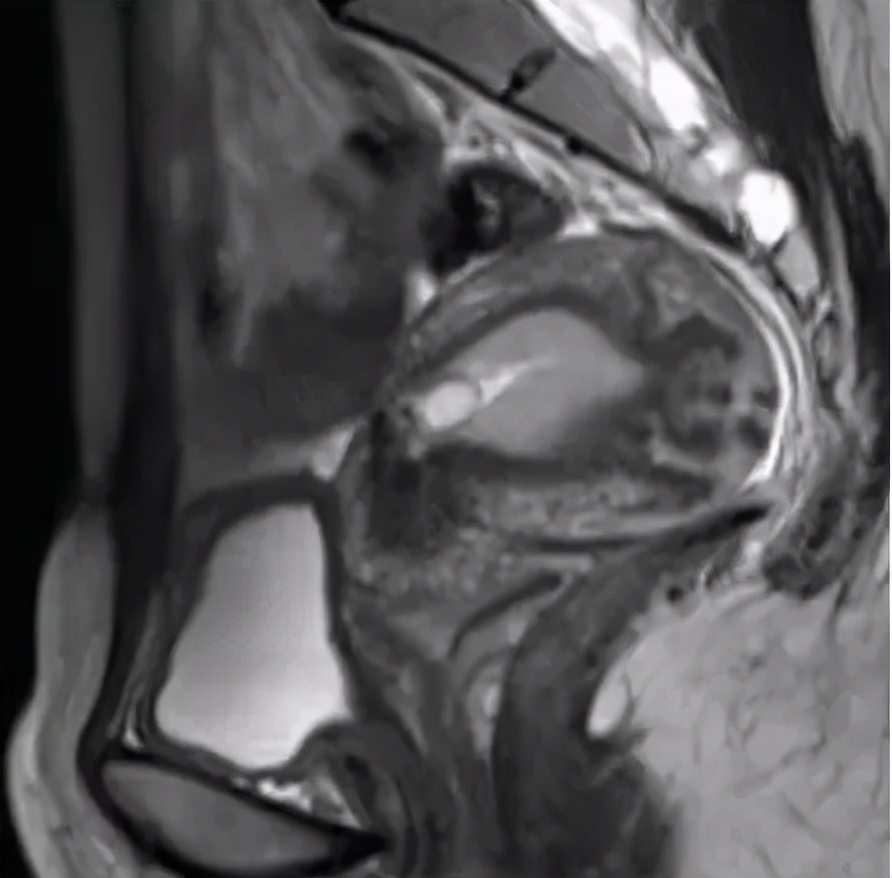

图1 瘢痕妊娠,显示妊娠囊位于子宫下段前壁瘢痕处,子宫肌层明显变薄。

磁共振(MRI)可获取 多方位、高组织对比度、高信噪比图像,而且安全无X线辐射 ,可清晰显示瘢痕处肌层缺损情况及其周围的解剖关系,在瘢痕子宫显示、评诂方面有重要价值。